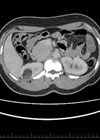

Case 1 A 28-year-old lady has been referred to your clinic with right loin pain. She has no significant past medical history but mentions that she and her partner have been trying to get pregnant. She has an US renal...